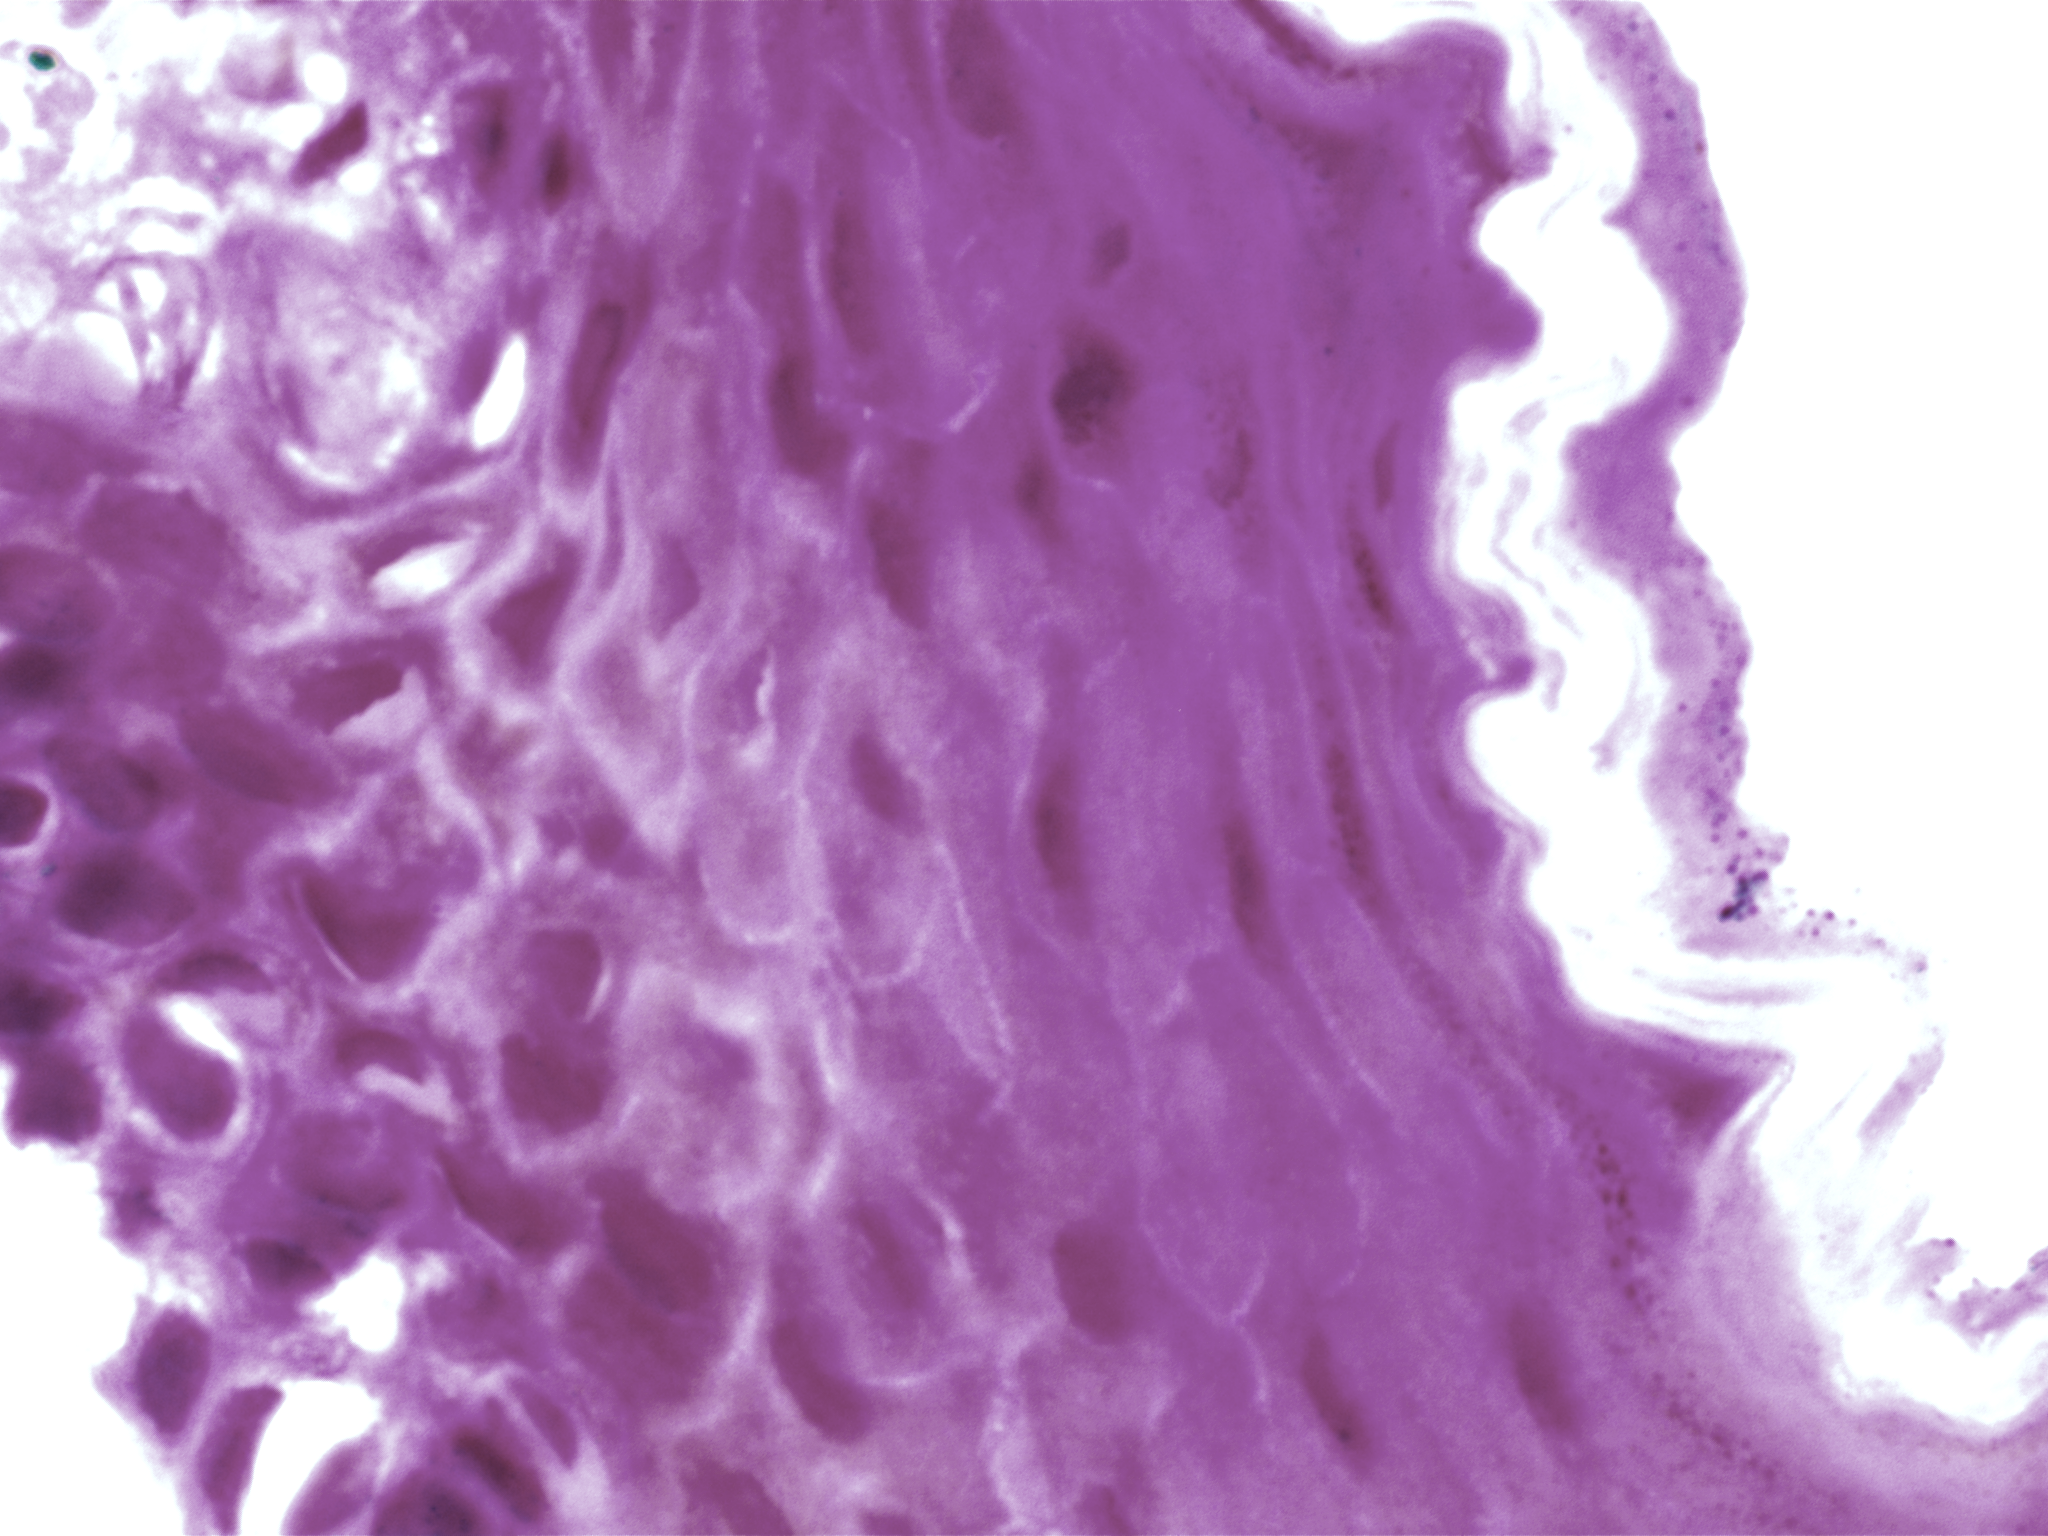

| Title: | High-resolution AI image dataset for diagnosing oral submucous fibrosis and squamous cell carcinoma |

| Description: | Oral cancer is a global health challenge with a difficult histopathological diagnosis. The accurate histopathological interpretation of oral cancer tissue samples remains difficult. However, early diagnosis is very challenging due to a lack of experienced pathologists and inter- observer variability in diagnosis. The application of artificial intelligence (deep learning algorithms) for oral cancer histology images is very promising for rapid diagnosis. However, it requires a quality annotated dataset to build AI models. We present ORCHID (ORal Cancer Histology Image Database), a specialized database generated to advance research in AI-based histology image analytics of oral cancer and precancer. The ORCHID database is an extensive multicenter collection of high-resolution images captured at 1000X effective magnification (100X objective lens), encapsulating various oral cancer and precancer categories, such as oral submucous fibrosis (OSMF) and oral squamous cell carcinoma (OSCC). Additionally, it also contains grade-level sub-classifications for OSCC, such as well- differentiated (WD), moderately-differentiated (MD), and poorly-differentiated (PD). The database seeks to aid in developing innovative artificial intelligence-based rapid diagnostics for OSMF and OSCC, along with subtypes. |

| Imaging Type: | Histopathology (HISTO) |

| The ORCHID database is an extensive multicenter collection of high-resolution images captured at 1000X effective magnification (100X objective lens). Tissue slides were collected with the approval of an ethical committee from the participating hospitals and research institutions. The buccal mucosa tissue samples were collected for three classes, normal, OSMF, and OSCC, with grade-wise annotation from the pathologists at each hospital. Biopsy samples of normal, OSMF and OSCC tissues underwent H&E staining. The staining procedure was conducted either in-house or outsourced to different laboratories. To eliminate staining variations across different laboratories, the preparation of H&E slides involved five histopathology labs, each utilizing their own independently developed and optimized protocols for the staining process. Following staining, the samples were examined under a microscope by a skilled histopathologist to assess cellular morphology, and tissue architecture, and identify any distinctive features or abnormalities specific to each sample type. This evaluation by the histopathologist involved grading the tissue slides for OSCC and OSMF, as well as differentiating between normal and diseased tissue sections. Images were acquired using a 1000X magnification (100X objective) lens from Leedz microimaging (LMI) bright field microscopy. To capture the images consistently, we utilized ToupView imaging software, which was configured for automatic adjustments. This setting applies to both white balance and camera settings, thereby standardizing the image acquisition process across different slides. The images of the H&E stained slides were captured at 1000X magnification(100X objective lens). By setting the ToupView software to automatically adjust white balance and camera settings, we aimed to minimize human intervention and the variability it introduces. This approach ensures that the images are not only consistent but also replicable in different laboratory settings, provided similar equipment and software settings are used. We collected approximately 100–150 images per tissue slide, which were stored in PNG file format. |